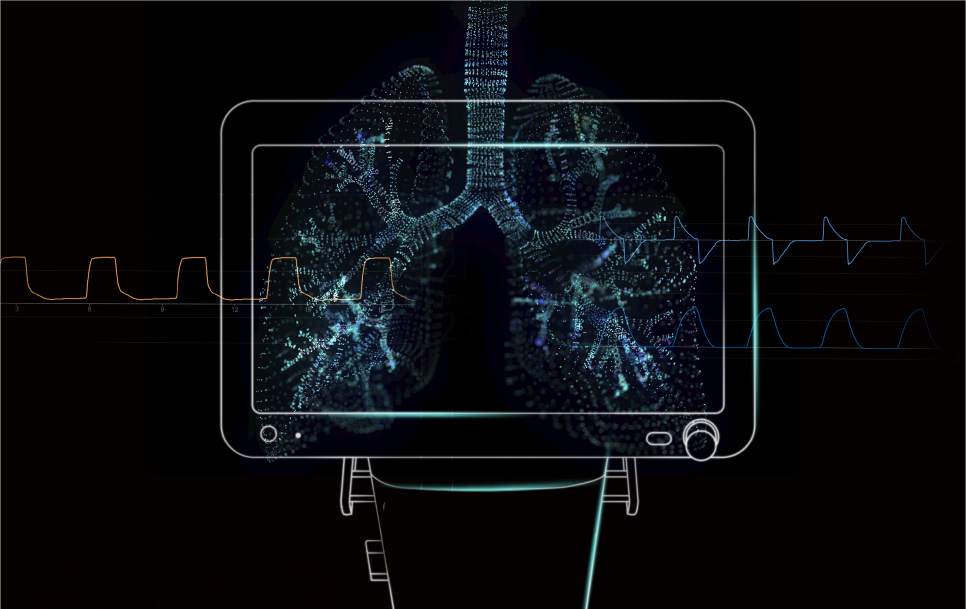

Puede haber desarrollos significativos durante el curso de una pandemia. La comunidad de medicina respiratoria fue la primera en soportar la peor parte de la pandemia provocada por la alta transmisibilidad del virus de la COVID-19 y por el rĂĄpido deterioro de la condiciĂłn de los pacientes. Los profesionales mĂ©dicos han profundizado su discusiĂłn sobre la facilidad de uso, la eficiencia y las caracterĂsticas de protecciĂłn pulmonar de los respiradores. En el futuro, lograr un equilibrio entre la seguridad y la eficiencia de la aplicaciĂłn clĂnica de los respiradores y reducir aun mĂĄs las barreras para la capacitaciĂłn sobre respiradores y su uso serĂĄn los problemas que no se podrĂĄn ignorar durante el desarrollo de estos dispositivos para cuidados intensivos en la era posterior a la epidemia.

El escritor francĂ©s Gustave Flaubert dijo una vez: âLa ciencia y el arte se separan al pie de la monta?a y se encuentran en la cimaâ. La terapia de ventilaciĂłn mecĂĄnica es el arte de la âconexiĂłnâ: los modos de ventilaciĂłn conectados con las exigencias del tratamiento clĂnico; el funcionamiento de los respiradores conectado con el esfuerzo de respiraciĂłn espontĂĄnea del paciente; la parametrizaciĂłn conectada con los indicadores mecĂĄnicos pulmonares del paciente; los tiempos de intubaciĂłn y extubaciĂłn conectados con los signos vitales del paciente; etcĂ©tera. DetrĂĄs de la conexiĂłn estĂĄ el dilema entre eficiencia y seguridad.

Sin embargo, con la ayuda de la IoT, los algoritmos, la IA y otras tecnologĂas avanzadas, el mundo mĂ©dico tambiĂ©n estĂĄ presenciando un momento decisivo. En el futuro, la innovaciĂłn de los respiradores se centrarĂĄ en la informatizaciĂłn mĂ©dica y la inteligencia de mĂĄquinas individuales a fin de aliviar continuamente la carga del personal mĂ©dico y brindar a los pacientes tratamientos mĂĄs precisos para lograr una mejor recuperaciĂłn.

Al centrarse en el concepto de protecciĂłn pulmonar precisa, Mindray se ha esforzado por brindar apoyo en la toma de decisiones clĂnicas en todo el proceso de intubaciĂłn, mediciĂłn y evaluaciĂłn, soporte de ventilaciĂłn y extubaciĂłn, con el fin de mejorar la seguridad clĂnica. Sobre la base de la integraciĂłn de datos de cabecera con el respaldo de algoritmos avanzados, las herramientas de apoyo de la toma de decisiones de los respiradores ayudan al personal clĂnico a evaluar los indicadores de los pacientes de manera mĂĄs integral. Al identificar los movimientos respiratorios del paciente y evaluar su reexpansiĂłn pulmonar con mayor precisiĂłn, el personal clĂnico puede optar por los tratamientos mĂĄs adecuados para facilitar la recuperaciĂłn.

Por supuesto, contar con dispositivos mĂĄs potentes y mĂĄs informaciĂłn no significa que los operadores deban cumplir con mĂĄs requisitos. En cambio, los respiradores estĂĄn pasando a ser medios de ventilaciĂłn inteligentes de circuito cerrado, al igual que los autos inteligentes estĂĄn en camino a la conducciĂłn autĂłnoma. Al lograr progresivamente la âidentificaciĂłn automĂĄticaâ del patrĂłn de respiraciĂłn del paciente y el âajuste automĂĄticoâ de los parĂĄmetros de ventilaciĂłn, los respiradores inteligentes mejoran la eficiencia clĂnica y la sinergia entre el respirador y el paciente. Con la ayuda de respiradores inteligentes, los cuidadores pueden abordar mejor muchas circunstancias en situaciones de cuidados agudos, con anestesia e intensivos y reducir la repeticiĂłn de los ajustes de los modos y parĂĄmetros de ventilaciĂłn para garantizar mejor la seguridad de los pacientes.